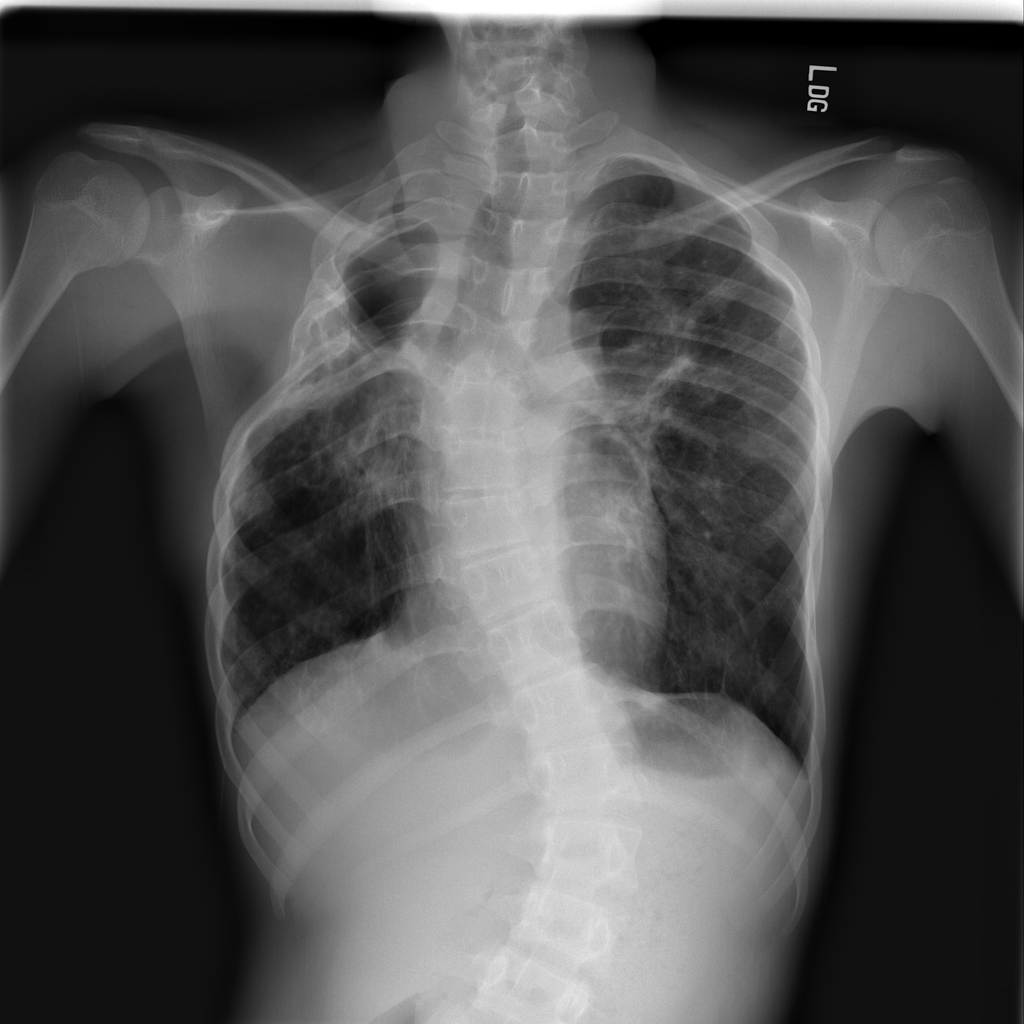

PAT-B3C3 · IMG-001Pneumonia

PAT-B3C3 · IMG-001

PA